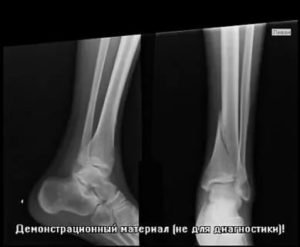

- Рентгенография. У детей старшего возраста при 2 и 4 типах перелома на снимках просматривается фрагмент метафиза, выявляется смещение ядер окостенения в эпифизарной зоне. У пациентов младшей возрастной группы и больных с остальными типами переломов изменения отсутствуют или нерезко выражены, поэтому в сомнительных случаях выполняют сравнительные рентгенограммы обеих конечностей.